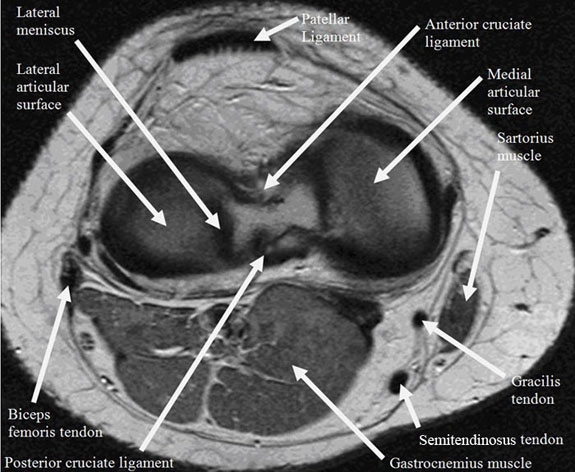

ACL, PCL

Sartorius

The sartorius muscle is the longest muscle in the body. It originates from the anterior iliac spine and inserts into the pes anserinus of the anteromedial tibia shaft near the tibial tuberosity. Pes anserinus bursitis commonly occurs in runners and causes anteromedial knee pain.

The tendon of the biceps femoris (part of the hamstrings) inserts at the styloid process of the head of the fibula. The medial condyle of the tibia is the insertion site for the semimembranous muscle, the most medial of the hamstring muscles. The hamstring muscles are involved in knee flexion and hip extension.